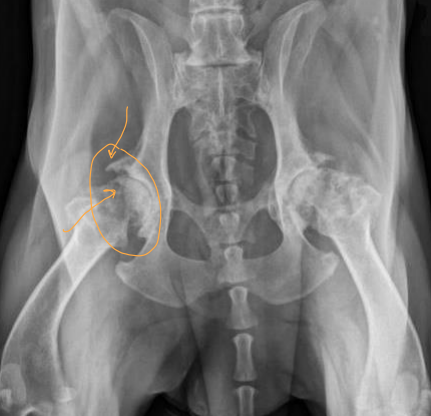

Diagnostic Imaging for Hip Dysplasia

VD most useful

Want >50% acetabular coverage!

Rads: Bone shape, remodeling, osteophytosis(neck), enthesiophytosis (Morgan’s line), laxity

Do not treat the radiograph!